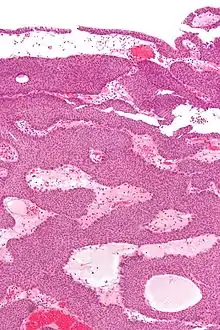

Micrograph of an inverted papilloma of the urinary bladder. H&E stain.

An inverted papilloma, also known as Ringertz tumour,[1] is a type of tumor in which surface epithelial cells grow downward into the underlying supportive tissue. It may occur in the nose and/or sinuses or in the urinary tract (bladder, renal pelvis, ureter, urethra). When it occurs in the nose or sinuses, it may cause symptoms similar to those caused by sinusitis, such as nasal congestion. When it occurs in the urinary tract, it may cause blood in the urine.